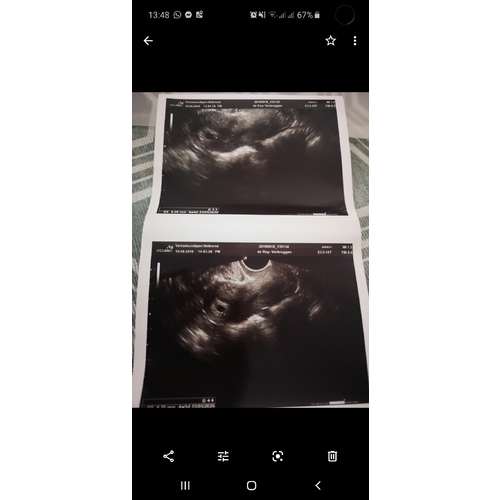

Deze in week 4 al gehad toen ik dacht in week 6 re zitten haha nu zit ik pas op week 6